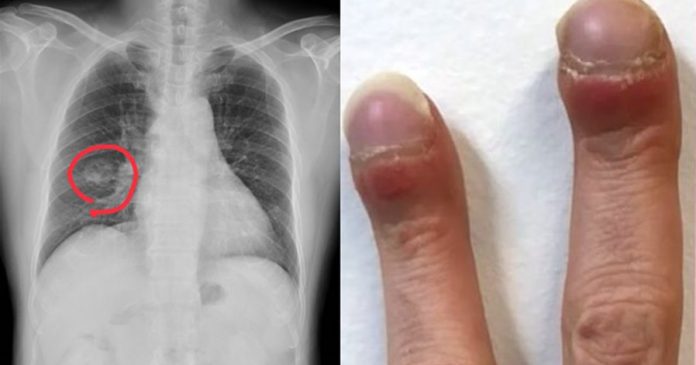

另外,洪永祥观察到妇人有「杵状指」,5根手指头像鼓棒一样,「这就是不对」。健康的人若将两根手指指甲对靠,应该留有缝隙,但杵状指因为指头圆滚滚,因此会紧密贴合、没有任何缝隙,这可能是缺氧现象。

依据上述2异状,他建议妇人照X光及心电图检查,「结果诊断出来是肺腺癌」,所幸为早期,开完刀持续追踪中。

1.杵状指

当发现手指末梢指节都圆滚滚「像鼓棒一样」,大多是心肺功能不好的表现,可能有心脏衰竭或长期贫血,建议就医检查。